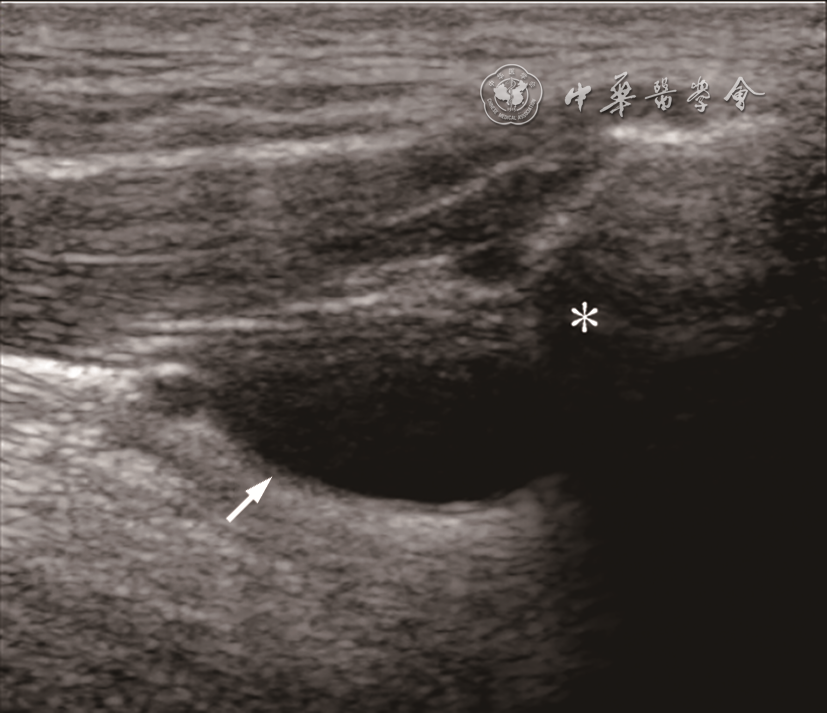

1.甲状舌管囊肿。甲状舌管囊肿是颈部最常见的先天性囊性病变,通常位于颈中线附近,大部分位于甲状腺和舌骨之间。甲状舌管囊肿声像图表现为边界清晰的无回声囊性病变,后方回声增强。病程长或合并感染时,内部回声增多,可见点状、片状回声,部分呈现类实性回声。甲状舌管囊肿与舌骨的粘连非常常见(图9),动态超声检查中肿物与舌骨的同步运动可作为甲状舌管囊肿的诊断依据之一8。CT或MRI也可用于评估甲状舌管囊肿,但超声检查相对更容易进行,且费用低、无创,儿童也无需镇静9

图9 甲状舌管囊肿超声图像。图示病变(箭头所示)与舌骨(星号所示)关系密切,位于舌骨头侧,动态观察可见病变随舌骨一起运动